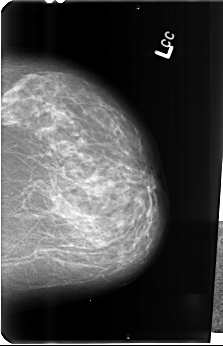

B_3488_1.LEFT_MLO

B_3488_1.LEFT_CC

LEFT_MLO LINES 4608 PIXELS_PER_LINE 3104 BITS_PER_PIXEL 12 RESOLUTION 50 NON_OVERLAY

LEFT_CC LINES 4832 PIXELS_PER_LINE 3120 BITS_PER_PIXEL 12 RESOLUTION 50 NON_OVERLAY